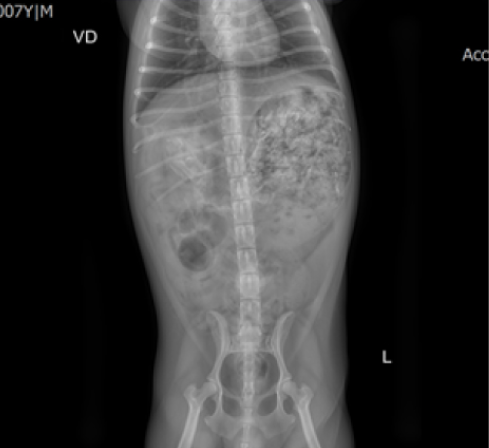

입원 4시간 후 촬영한 x-ray 사진에서 위 내용물의 변화가 없었으나 다행히 안락동동물병원 리본동물의료센터는 이 아이가 소화제를 먹고 오전 8시경 찍은 x-ray에서 내용물이 조금씩 내려가는 것을 확인할 수 있었습니다.

하지만 소화기관을 통해서 내려가는 와중에도 손상을 일으킬 수 있으므로 퇴원 후에도 변 상태, 구토, 설사 등 임상증상 발생 여부 등을 모니터링하여야 합니다.